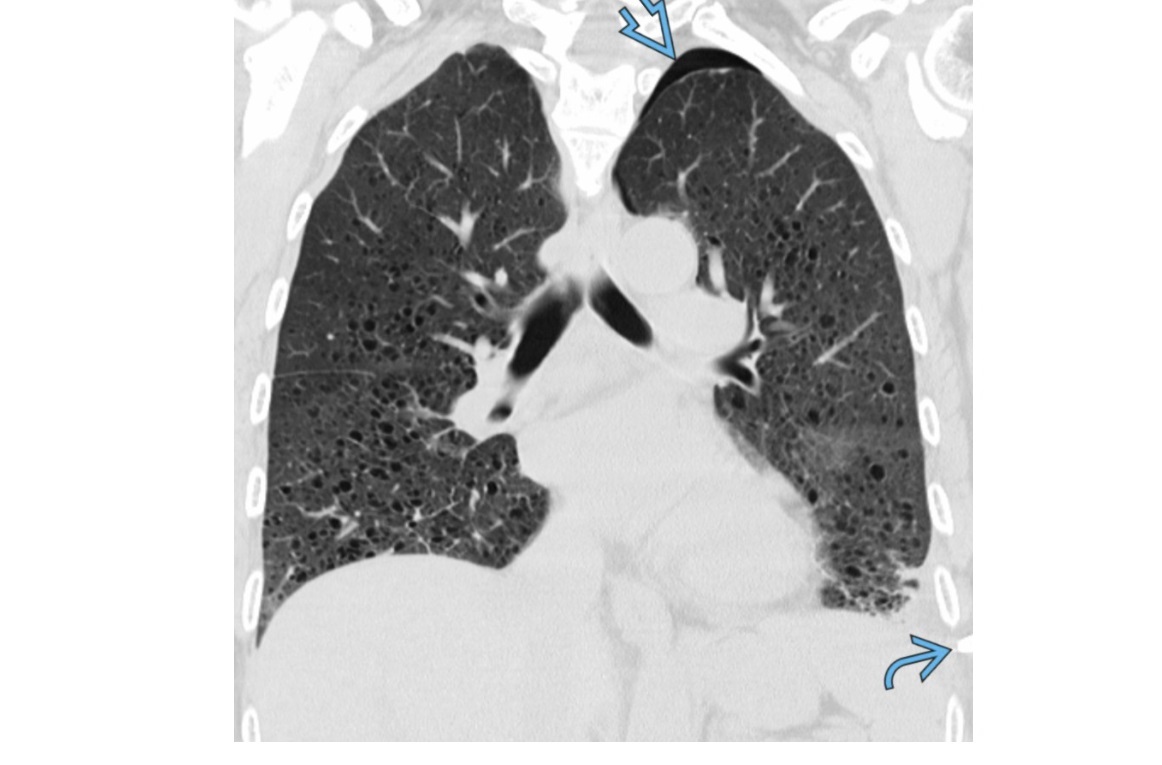

Lymphangioleiomyomatosis (LAM)

Diffuse no lobe predominant Thin walled cysts

Spontaneous PTX

Premenopausal women

NORMAL lung volumes

Chylous pleural effusions

increased lung volumes

Associated with tuberous sclerosis - 1/3rd have AMLs

Pulmonary Langerhans cell histiocytosis (PLCH)

Predominant upper lobes

bizarre-shaped thick pulmonary cysts

Smokers

Early stages of disease, 1-10mm nodules in mid/upper zone predominant

M:F =

Effusions are rare

Sparing costophrenic angles